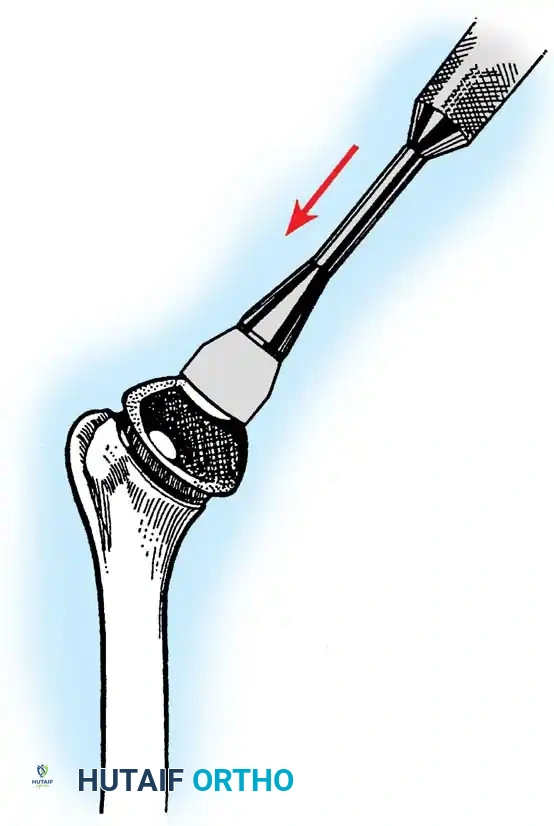

2. Joint Preparation

The tip of the olecranon is excised to facilitate access to the medullary canal. The distal humerus is prepared by resecting the trochlea and capitellum, preserving the epicondyles if possible to maintain collateral ligament attachments (though less critical in linked designs).

3. Canal Preparation and Implantation

The humeral and ulnar canals are sequentially broached.